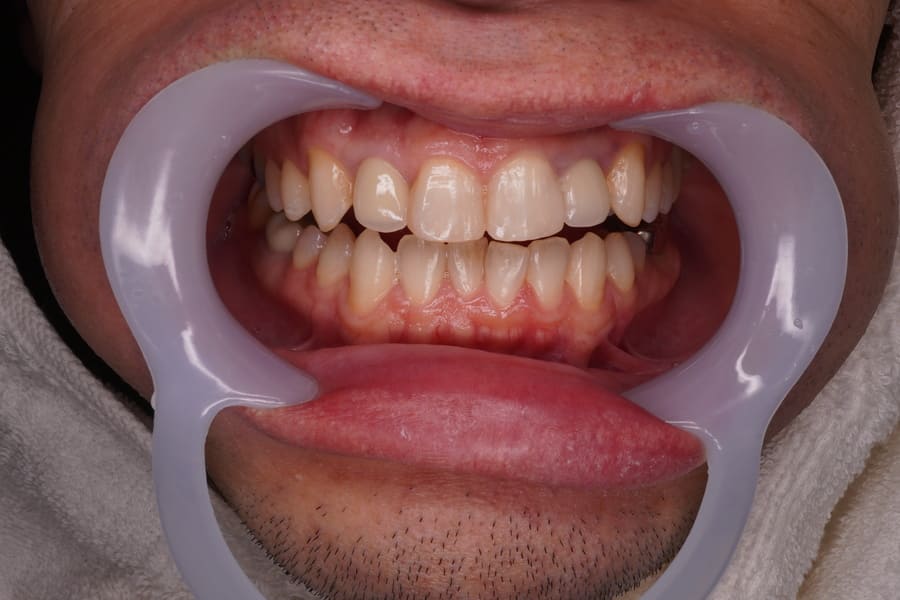

Before

After

主訴 左上のセラミックの歯の歯ぐきが下がって変色した歯が出てきて見た目が気になるのでやり直したい。 性別 女性 年齢 50代 症例概要・補綴専門医としての分析 ・50代女性

・左上5番にオールセラミッククラウンが装着されている。

左上4番にはインプラントによるオールセラミッククラウンが装着されている。

頬側の歯肉退縮が生じており歯頸部に黒変した歯質が露出して審美障害を生じている。

全体的な辺縁不適合が認められた。

セラミック咬合面には若干の咬耗が認められた。

左上5番頬側歯肉辺縁に発赤・腫脹は認められない。

エックス線から歯根に問題は認められなかった。

患者さんには、過度にブラッシングする習慣があり、ブラッシング圧とブラッシング時間のコントロールを指導した。

また、クレンチングの習癖があり、生活指導及びナイトガードの夜間使用をお願いしている。

これらのご指導・お願いが実施されることを前提に、咬合力の強くない女性であること、審美性を重視していることなどからモノリシックジルコニアクラウンではないジルコニアフレームにポーセレンを積層する方法、ジルコボンドクラウンにて再補綴することとした。

【ジルコボンドクラウン】

強度の高いジルコニアフレームに、見た目の美しいセラミック(ポーセレン)を焼き付けた2層構造の被せ物

「ジルコニアセラミック」「レイヤードジルコニア」とも呼ばれます。

辺縁歯肉の退縮の原因は、歯ブラシによる力の影響とクレンチングによる影響と考えられる。

歯周基本治療を行いながら左上5番に装着されているオールセラミッククラウンを除去した。

装着されているレジン築造に不適合が認められたため、形態修正後再度レジン築造を行った。

支台歯形成後、プロビジョナルレストレーションを製作、仮着して辺縁歯肉の反応等を次回来院時まで経過観察した。

辺縁歯肉の状態は安定しているので、

形態的・色調的問題を患者さんに確認、同意が得られたため最終補綴へ移行した。

印象採得、咬合採得を行い補綴物を製作した。

完成したオールセラミッククラウンの近遠心コンタクトの調整を行い、その後咬合チェックして咬合調整・研磨を行った。

ジルコボンドクラウンを試適して患者さんに鏡で見て頂き問題がないことを確認後、合着を行った。合着1週間後に各種チェックを行い若干の調整、研磨を行った。治療期間・回数 治療期間4週間で3回来院。 術前(2026年2月)術後(2026年3月) 費用

(自由診療となります)総額 自由診療154000円(税込み) 診査・診断・プロビジョナルレストレーション・術前術後の説明費用含む。 リスク・副作用 セラミックの破折、脱離。歯肉の退縮。根の病気。

術後の対策 補綴専門医の視点 今後、辺縁歯肉の退縮を避けるための方策を検討し患者さんと対応を共有することとした。

必ず3か月ごとの予後観察に来院していただくよう依頼した。